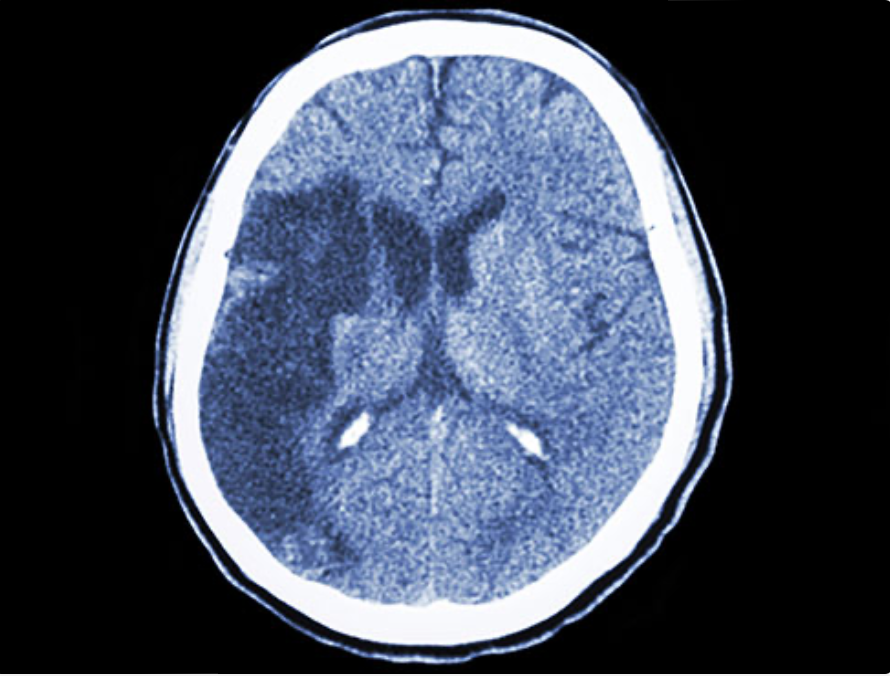

The UAB Comprehensive Stroke Center has been recertified by the Joint Commission. UAB was originally designated a Comprehensive Stroke Center by the Joint Commission and the American Heart Association/American Stroke Association in 2015. This designation identifies UAB as an industry leader responsible for setting the national agenda in highly specialized stroke care.brain strokeBrain scan of stroke patient

An American has a stroke every 40 seconds, and someone dies from a stroke every four minutes. A stroke occurs when a blood vessel is either blocked by a clot or bursts, interupting blood flow, and deprives brain cells of the oxygen and nutrients they need to survive. Strokes are the fifth-leading cause of death and a leading cause of adult disability in the United States.